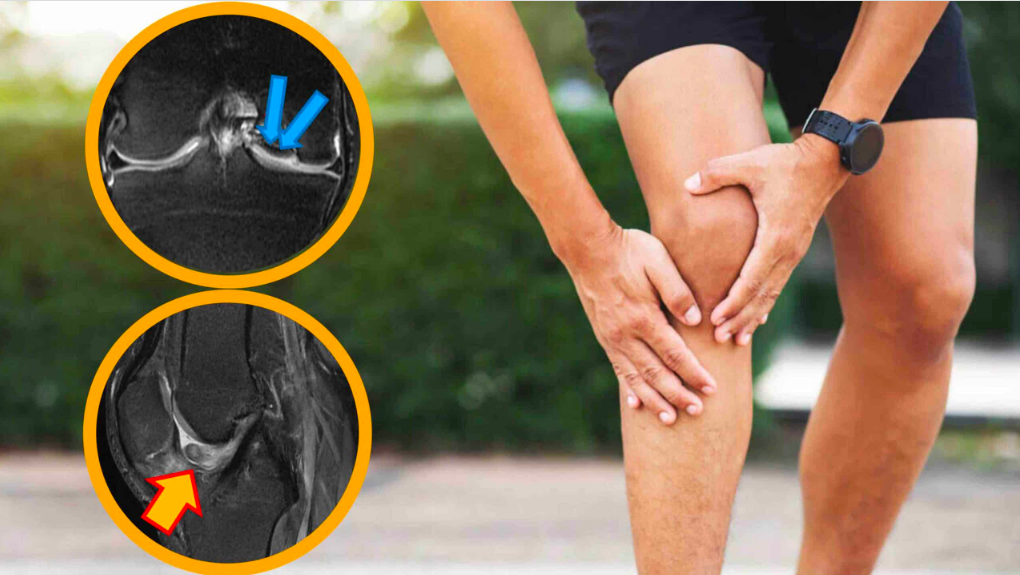

Dor no joelho: 5 sinais que mostram quando é apenas sobrecarga e quando pode ser algo mais sério | Foto: (Reprodução/Internet)

“Falseio, sensação de algo ‘preso’ dentro do joelho, limitação de movimento e inchaço recorrente indicam que a estrutura articular precisa ser investigada muitas vezes com ressonância”, enfatiza o médico.